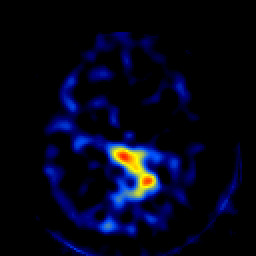

SPECT TL Study #4 -- Slice #40

[Home][Help][Clinical][Tour 1][Tour 2][Tour 3] Slice 40